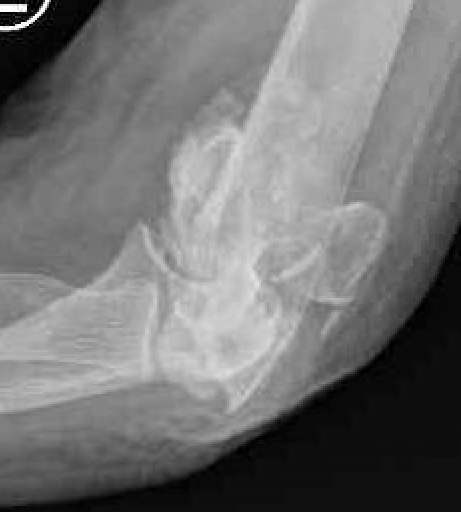

Bag of bones / nonoperative management

Initial injury in elderly patient

Elbow post treatment in cast

Indication

Patient elderly and not operative candidate

Technique

Initial rest in plaster then mobilisation

Results

- 40 "elderly and low demand" patients treated non-op

- 5 year mortality 40%

- 50% non union

- DASH score 38/100

- modest function, but avoids risks